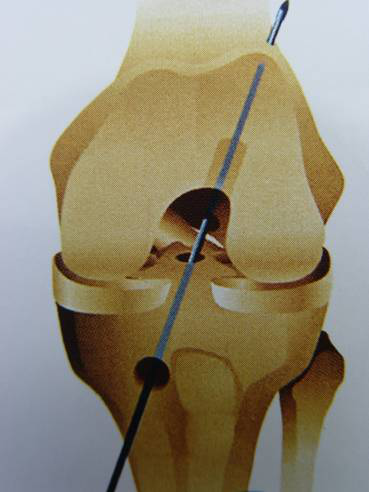

脛骨點(diǎn)選取

股骨點(diǎn)